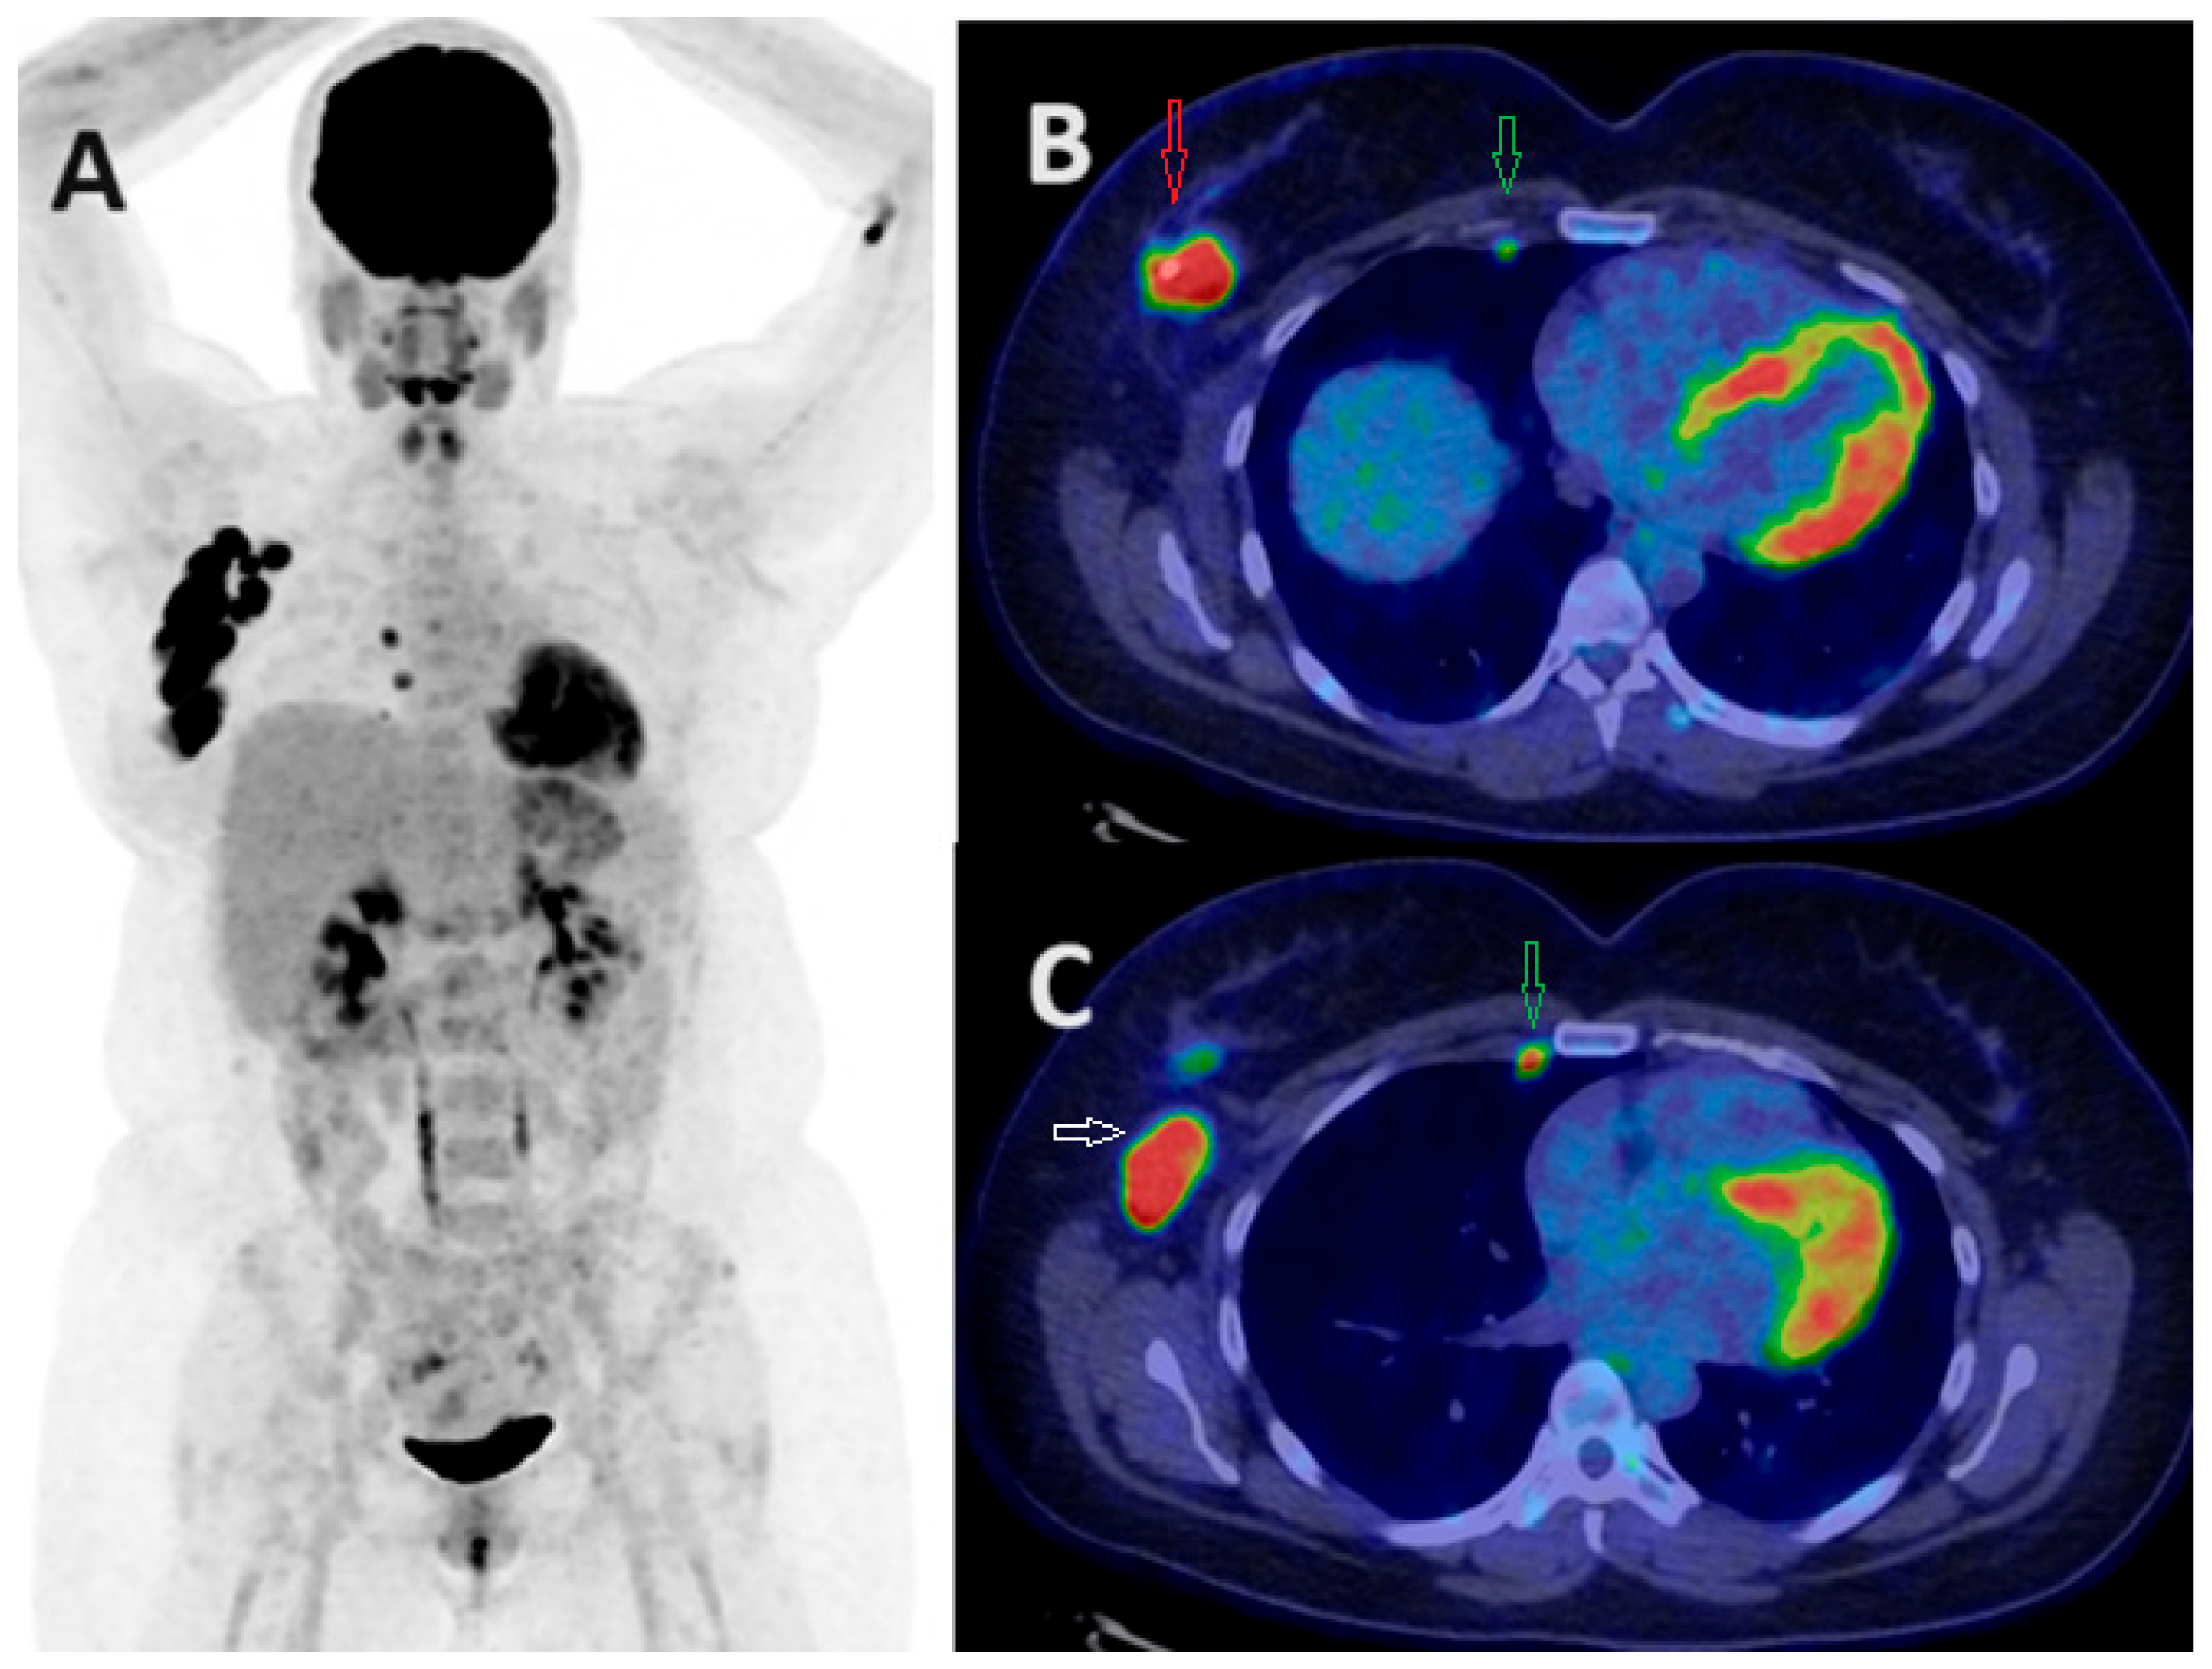

- Elboga, U.; Sahin, E.; Kus, T.; Cayirli, Y.B.; Aktas, G.; Uzun, E.; Cinkir, H.Y.; Teker, F.; Sever, O.N.; Aytekin, A.; et al. Superiority of 68Ga-FAPI PET/CT scan in detecting additional lesions compared to 18FDG PET/CT scan in breast cancer. Ann. Nucl. Med. 2021, 35, 1321–1331. [Google Scholar] [CrossRef] [PubMed]

- Evangelista, L.; Filippi, L.; Schillaci, O. What radiolabeled FAPI pet can add in breast cancer? A systematic review from literature. Ann. Nucl. Med. 2023, 37, 442–450. [Google Scholar] [CrossRef] [PubMed]